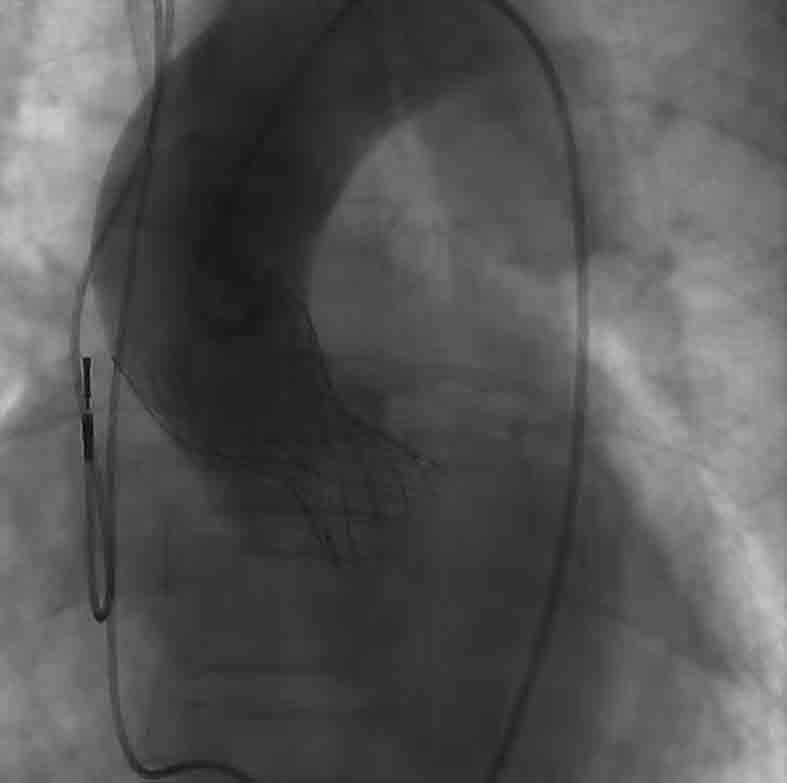

在北京阜外医院攻读研究生和博士后期间,裴汉军一直从事经导管主动脉瓣置入术的临床和科研工作,积累了丰富的经验。为保证手术万无一失,裴汉军特邀请北京阜外医院的恩师吴永健团队前来助阵。经过精心准备,手术于10月30日如期进行,成功将一枚人工心脏生物瓣膜置入患者心脏,同时还为其置入了一枚心脏支架,手术难度和手术风险均达到极高的水平。术后半小时,患者就完全清醒,第二天就可以自如地下地活动。